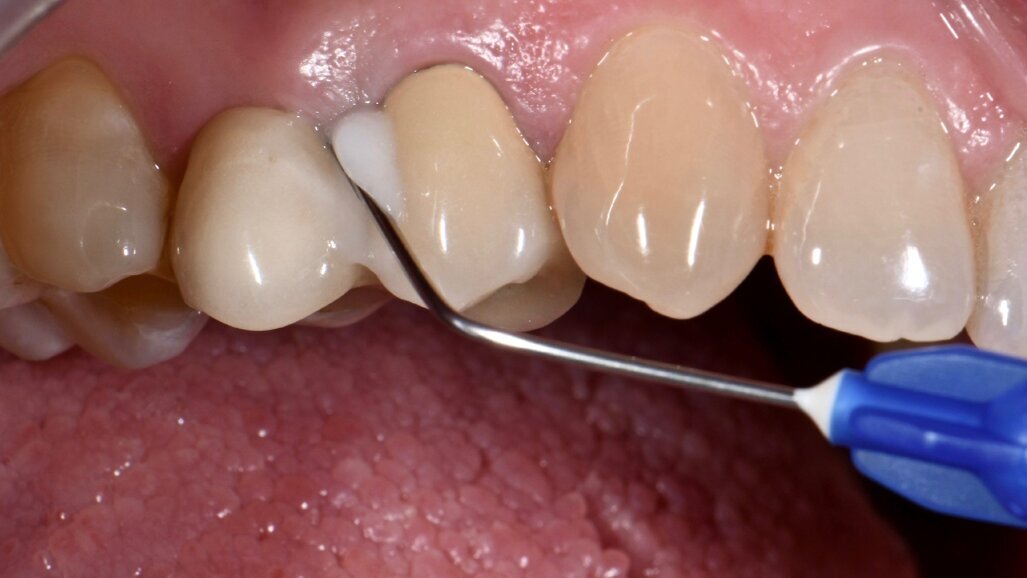

Materiali e metodi Case report Il presente case report è stato redatto in accordo con il CARE checklist (https://www.carestatement.org/checklist, consultato il 29 Gennaio 2024). Una paziente italiana di 44 anni, non fumatrice si è recata alla S.C Riabilitazione Orale Protesi Maxillo-Facciale e Implantologia Dentaria della Dental School dell’Università degli Studi di Torino nel mese di Gennaio 2023, lamentando sanguinamento gengivale durante lo spazzolamento. La paziente ha firmato un consenso informato. L’anamnesi medica della paziente non era rilevante. All’esame intraorale si evidenziava una scarsa igiene orale e la presenza di impianti in sito 15 e 25 (Figg. 1a-1c). I parametri parodontali al baseline sono stati riportati in Figura 2.

Fig. 1a - Condizione clinica al baseline: visione frontale.

Fig. 1b - Condizione clinica al baseline: I e VI sestante.

Fig. 1c - Condizione clinica al baseline: III e IV sestante.

Il Full Mouth Plaque Score (FMPS) era 71%, il Full Mouth Bleeding Score (FMBS) era 24% ed è stata osservata una profondità di sondaggio ≥ 4 mm nel 9,5% dei siti, localizzata a livello dei molari e premolari di entrambe le arcate. L’impianto in situ 15 (Nobel Replace, diametro 4,3mm, lunghezza 13mm) e l’impianto in situ 25 (Sweden & Martina SYRA, diametro 4,25 mm, lunghezza 1 mm) presentavano placca e una mucosa peri-implantare eritematosa ed edematosa. Per ciò che concerne l’impianto 15, si era riscontrata una moderata (PPD 4-5 mm) e severa (PPD≥ 6 mm) profondità di sondaggio, con una profondità media di 3.33 mm. FMBS e FMPS erano del 100%, così come riportato in Figura 2. La rilevazione dei parametri peri-implantari dell’impianto 25 aveva evidenziato PPD moderati nel 67% dei siti e una PPD severa a livello mesio-vestibolare. FMPS e FMBS erano 100%.